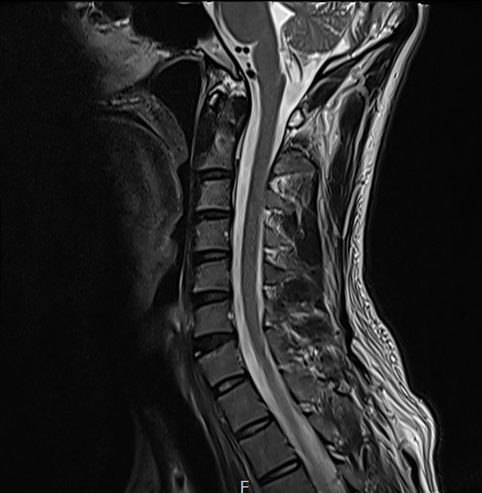

이 환자분은 경추 MRI를 촬영했어요.

어지럼증이 있는데 목을 찍는다는 생각에…

처음에는 불편해하셨어요 ㅜㅜ 이해합니다.

하지만 결과는 거짓말을 하지 않죠.

목디스크 및 협착증 소견이 나왔어요.

그림9.png 촬영 일시: 2025.05.29

<Fig 1. 경추 디스크로 진단된 mri 영상>

환자분은 처음에 되게 의외해하시더라고요.

어... 목 때문에 머리가 어지러울 수 있나요?

저는 목은 별로 안 아픈데...